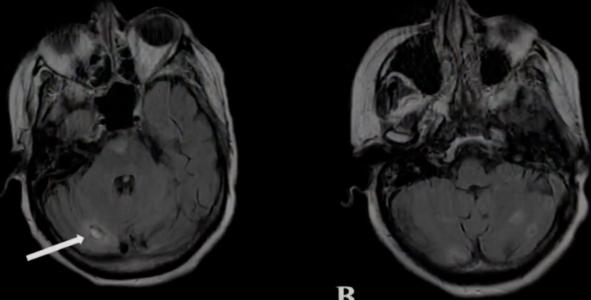

A 71-year-old woman in Texas died from a rare brain-eating amoeba (Naegleria fowleri) after rinsing her nose with tap water from an RV at a campground. Image source: KGW News / Youtube.